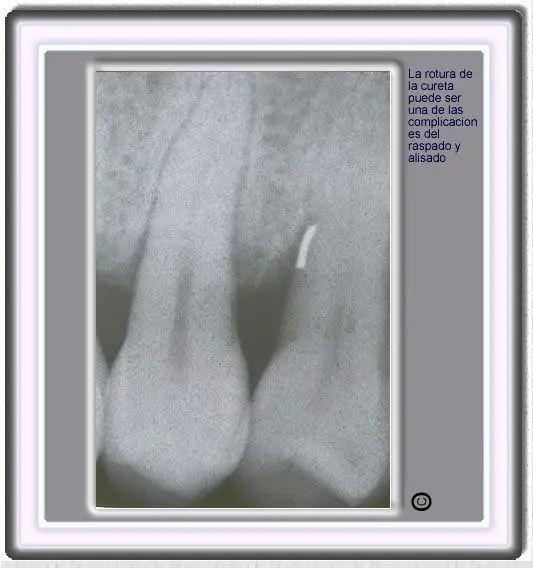

image333